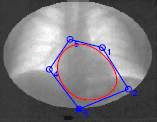

User-Defined B-Spline Template Snakes, T. McInerney , and H. Dehmeshki,

Sixth International Conf. on Medical Image Computing and Computer Assisted |

Interactive Medical Image Segmentation with United Snakes, J. Liang, T. McInerney and D. Terzopoulos, Second International Conference on Medical Image Computing and Computer Assisted Interventions (MICCAI99), Cambridge, England, September, 1999, pages 116-127. |

| 14. |  |

United Snakes (Towards a More Perfect Union of Active Contour Techniques), J. Liang, T. McInerney and D. Terzopoulos, IEEE Seventh International Conference on Computer Vision (ICCV99), Kerkyra, Greece, September, 1999, pages 933-940. |